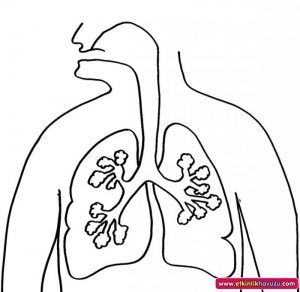

570x320 Outline Of Human Body Internal Organs

800x800 Lungs Doodle Drawing, Medical Background. Excellent Vector

1300x1294 Human Anatomy Of The Lungs Black And White Stock Photos Amp Images